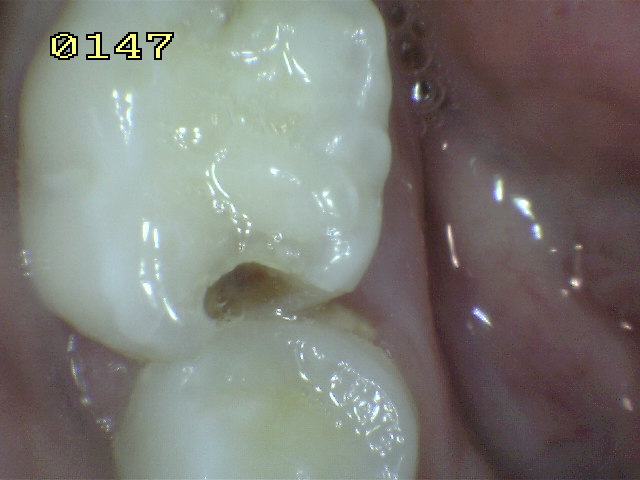

Finalmente, tanto la

información radiográfica (cuando está disponible para

dientes posteriores) y la valoración clínica terminan

clasificando la lesión en las categorías de inicial,

moderada o severa. Es importante reconocer la variación

entre países en cuanto a la definición de la severidad de la

lesión y su equivalencia radiográfica. Esta variación se

reducirá en la medida que haya más evidencia.

Finalmente, tanto la información

radiográfica (cuando está disponible para dientes

posteriores) y la valoración clínica terminan clasificando

la lesión en las categorías de inicial, moderada o severa.